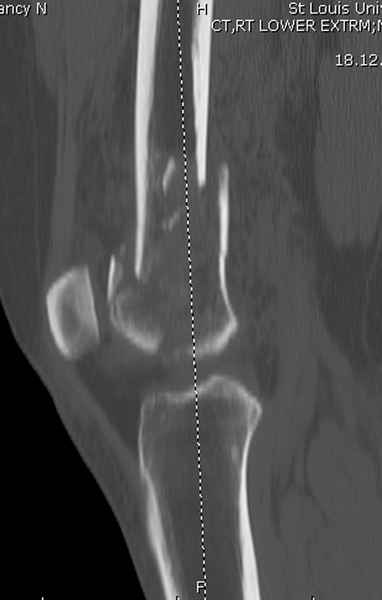

Приветствую всех коллег!!Во первых слева хотелось бы видеть четкую боковую проекцию а лучше КТ. По р-мам есть сомнения насчет повреждения суставной поверхности. При подобных переломах даже внутрисуставных без смещения хорошие результаты показал закрытый ретроградный остеосинтез универсальным бедренным стержнем Деост.Кстати при внутрисуставном переломе возможно применение вместо винтов стягивающих болтов!!(См. метод.Деост).При переломе справа также стержень Деост. Однако без открытия Вам не удастся устранить интерпозицию, только промучаетесь!Из минимального разреза удалите интерпозициб и фиксируйте стержнем. Причем универсальный стежень Деост позволяет фиксировать дистально минимум на трех уровнях!

Мы бы не стали открывать, такие переломы срастаются, хотя бы и с краевым дефектом. То есть если удалять стержень потом, то сильно попозже обычного. В приложении пример. Сразу после операции и через 11 мес. Понятное дело, пациент к тому времени давно и не хромал, и функция колена была полная.